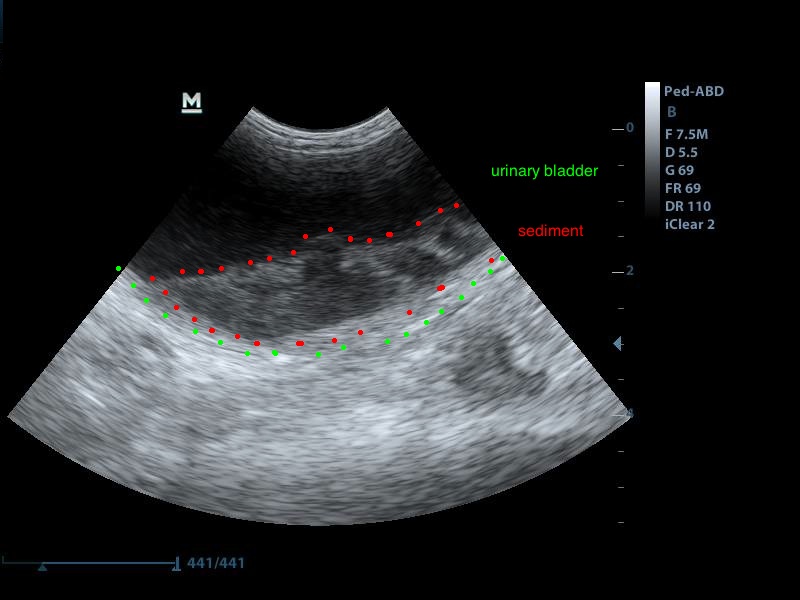

Ευρήματα: Στον υπέρηχο κοιλίας βρέθηκε επώδυνη διόγκωση και των δύο νεφρών με πάχυνση της φλοιώδους ουσίας, η οποία παρουσίαζε έντονη ανομοιογένεια. Οι νεφρικές πύελοι ήταν ήπια διατεταμένοι και στο εσωτερικό τους παρατηρήθηκε αφθονία ιζήματος. Οι ουρητήρες, οι οποίοι ήταν επίσης διατεταμένοι, απεικονίζονταν μέχρι την είσοδό τους στην ουροδόχο κύστη. Αφθονία ιζήματος βρέθηκε στην ουροδόχο κύστη. Η εικόνα αυτή είναι συμβατή με διάμεση νεφρίτιδα και στην συγκεκριμένη περίπτωση με πυοκοκκιωματώδη φλεγμονή των νεφρών, συνεκτιμώντας τα εργαστηριακά ευρήματα, τον έντονο πόνο και τη διάταση των ουρητήρων. Το resistive index ( δείκτης αγγειακής αντίστασης) βρέθηκε αυξημένο (0.77) σε μεσολόβιο αρτηρίδιο του νεφρού. Φυσιολογικά θα έπρεπε να είναι (0.6±0.06). Αυτό δείχνει πως το οίδημα του νεφρικού παρεγχύματος εξαιτίας φλεγμονής ή οποιαδήποτε άλλης διήθησης, νεοπλασματικής ή μη, πιέζει τα αγγεία και αυξάνει την αντίσταση του αίματος προς το νεφρό. Ένα επιπλέον διαγνωστικό βήμα για την διερεύνηση της αιτίας, για την αποτελεσματικότερη θεραπεία και την εγκυρότερη πρόγνωση, είναι η λήψη κυτταρολογικού υλικού από το νεφρικό παρέγχυμα και ούρου από τη νεφρική πύελο για καλλιέργεια, στα οποία ο ιδιοκτήτης δεν θέλησε να προχωρήσει.